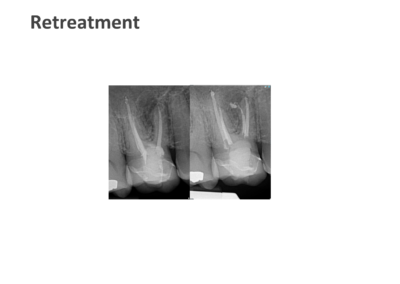

We take pride in providing the highest standard of care at ICE and believe that only the best is good enough for our patients. As such, Shakil completes all endodontic procedures using a state-of-the-art dental microscope. We accept referrals for consultations, root canal treatment (primary and retreatment), management of endodontic emergencies, dentoalveolar trauma and we are also happy to provide definitive restorations as required.